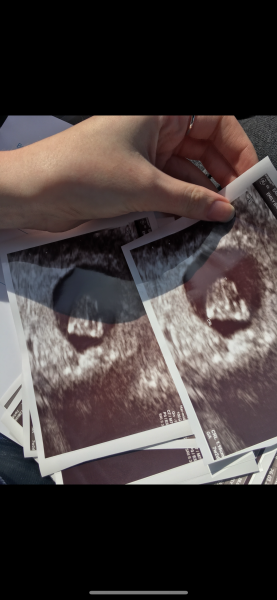

This was 7+3 with my DD.

Will be having a scan at 8 weeks this time :)

@Ems1992 thank you for sharing! That’s more than I thought! How far along are you at the moment?

Aw wow! I’ll come back here and share the photos! It’ll be interesting to compare how much they change over a couple of days!

@PineappleBella at 7 weeks with my previous 2 pregnancies I could see a little jelly bean shape with a lovely flickering heartbeat. It’s such a joyful moment. I’ve got my early scan in EPU on 27th I will be 8+4 it feels like a lifetime away